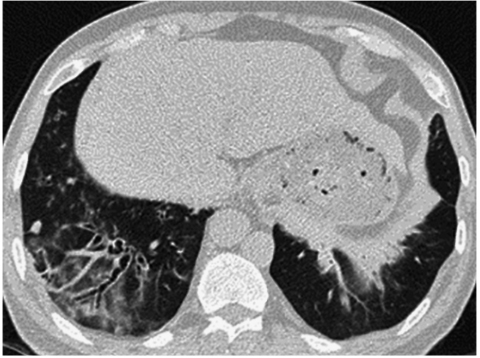

【随访】

患者明确诊断后院外口服药物治疗,咳嗽、咳痰、气急症状较前好转,2018年4月26日复查肺功能提示DLCO/pre 65.2%,较前相仿;动脉血气分析提示SaO2 95.8%,较前好转;胸部CT平扫:病灶较前有所吸收(图7)。

图7胸部CT平扫示双肺下叶基底段病灶较前明显吸收